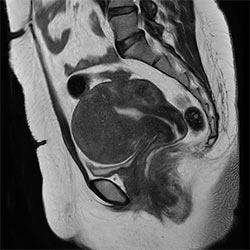

In a society where reimbursements are declining and chronic conditions lead to increased MR procedures and longer waiting times, there is ever increasing pressure on the radiology department. Today, further attempts to accelerate, compromise image quality or are limited to a narrow range of scans. Therefore, to meet the increased demand for productivity, a technology break-through in acceleration is still required. Leveraging our long standing leadership position in speed (i.e. SENSE), Philips brings compressed SENSE, a breakthrough in productivity.

Learn more about the main principles of Compressed SENSE and how it introduces a paradigm shift in productivity, how Compressed SENSE was designed around image quality, and how it advances productivity for clinical MR imaging.